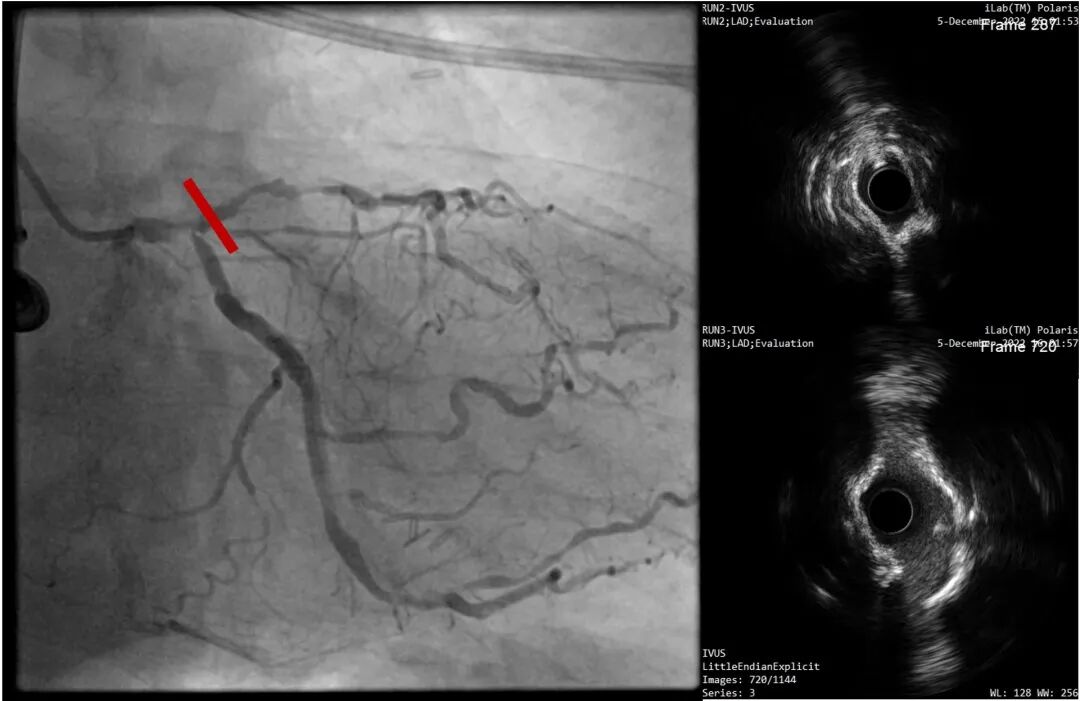

考虑到患者钙化严重且弥漫,为精准化钙化病变预处理方案,对患者进行IVUS检查,但超声导管无法通过病变部位;

病变部位旋磨后,振波后超声对比

LAD近段-LM IVUS提示为270°环形钙化

复查LAD近段-LM IVUS,钙化环明显断裂